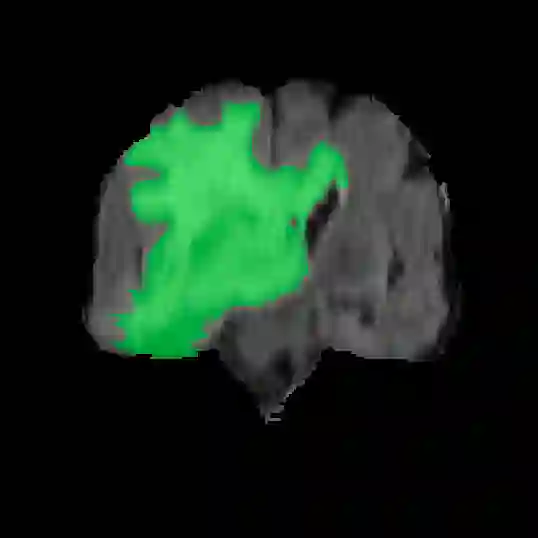

Automatic and accurate tumor segmentation on medical images is in high demand to assist physicians with diagnosis and treatment. However, it is difficult to obtain massive amounts of annotated training data required by the deep-learning models as the manual delineation process is often tedious and expertise required. Although self-supervised learning (SSL) scheme has been widely adopted to address this problem, most SSL methods focus only on global structure information, ignoring the key distinguishing features of tumor regions: local intensity variation and large size distribution. In this paper, we propose Scale-Aware Restoration (SAR), a SSL method for 3D tumor segmentation. Specifically, a novel proxy task, i.e. scale discrimination, is formulated to pre-train the 3D neural network combined with the self-restoration task. Thus, the pre-trained model learns multi-level local representations through multi-scale inputs. Moreover, an adversarial learning module is further introduced to learn modality invariant representations from multiple unlabeled source datasets. We demonstrate the effectiveness of our methods on two downstream tasks: i) Brain tumor segmentation, ii) Pancreas tumor segmentation. Compared with the state-of-the-art 3D SSL methods, our proposed approach can significantly improve the segmentation accuracy. Besides, we analyze its advantages from multiple perspectives such as data efficiency, performance, and convergence speed.